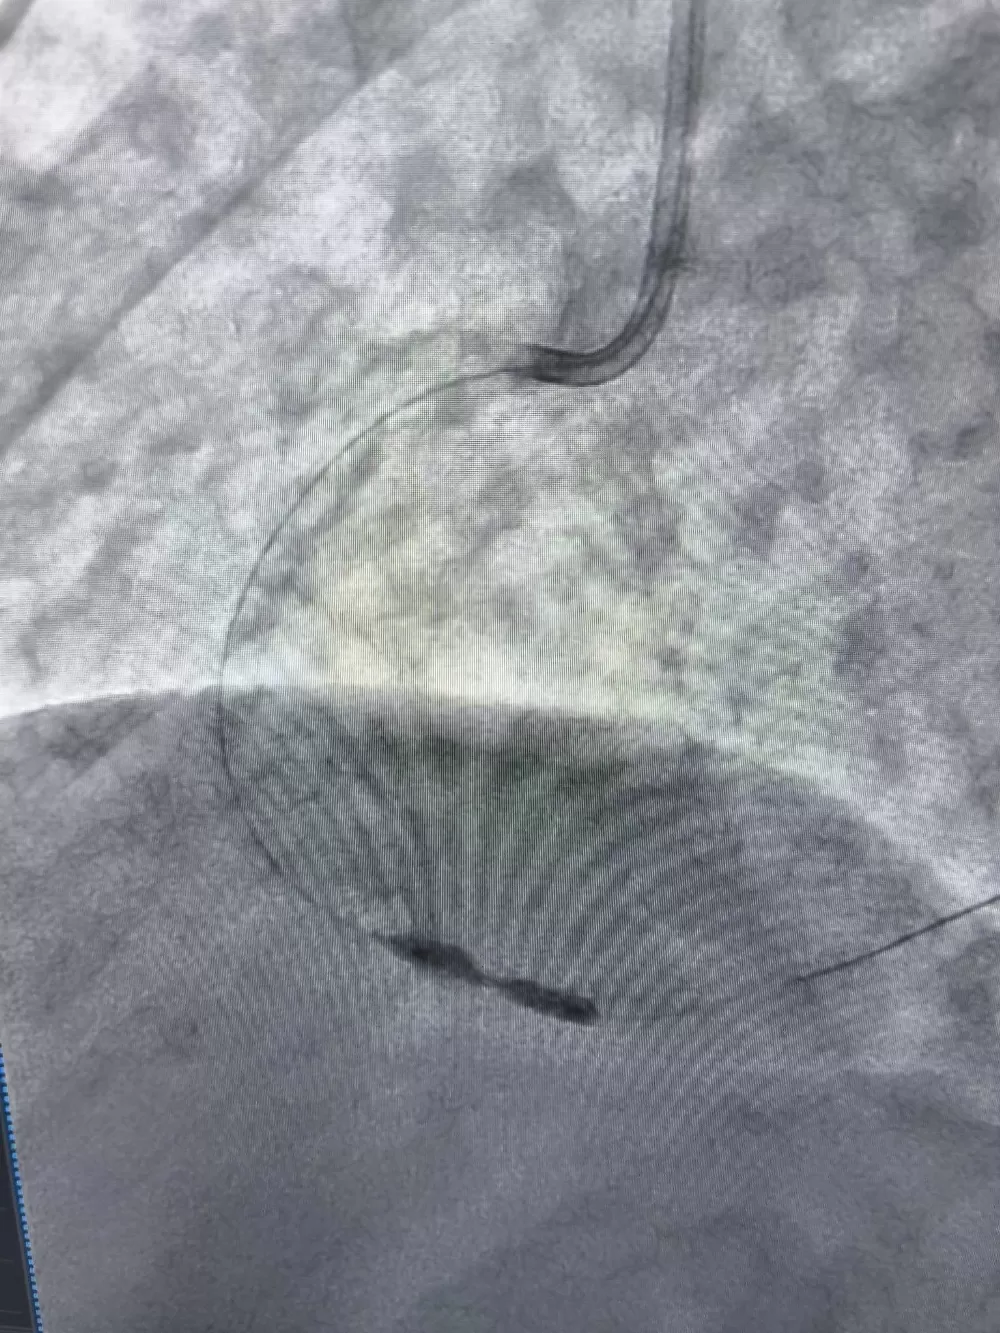

Тоді медики застосували ротаблятор. Це спеціальний прилад з буром, який покритий діамантовим напиленням. Він дозволяє обробити звапнілу бляшку в судині, фактично шліфуючи її. Після цього лікарі змогли встановити стенти.

Операція пройшла успішно. Жінці встановили стенти, які відновили нормальний кровотік у серцевій артерії.